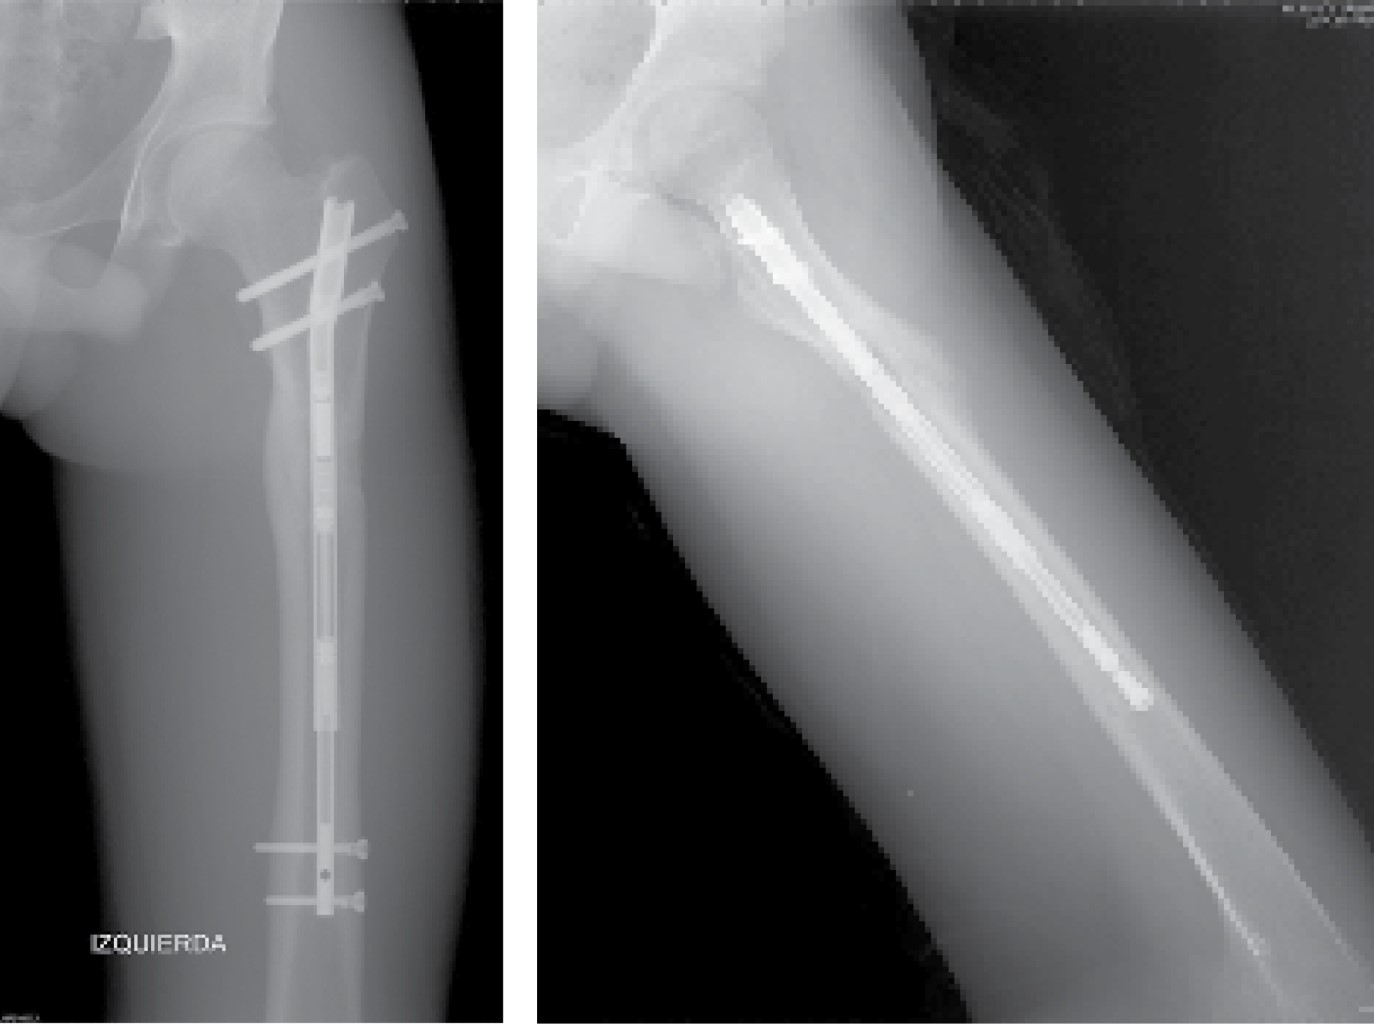

Se identificó el lugar de la osteotomía femoral siguiendo el método habitual descrito por Paley y colaboradores,13 realizándose mediante múltiples perforaciones a través de un abordaje lateral. Como describen algunos autores, estas perforaciones registran una baja tasa de tromboembolismo pulmonar.2 El punto de entrada del clavo se realizó en la punta del trocánter mayor a través de un abordaje lateral proximal (Figura 1), que permitió el fresado del canal femoral hasta 1.5-2 mm mayor que el diámetro definitivo del clavo seleccionado. Se introdujo el clavo intramedular Precice® hasta el borde proximal de la zona de osteotomía y se completó la misma a través del abordaje lateral, introduciendo el clavo hasta su localización definitiva y bloqueándolo proximal y distalmente (Figura 2). Por último, se realizó la distracción del clavo 1-2 mm para asegurar el correcto funcionamiento del dispositivo magnético.

Todos los pacientes fueron instruidos para el correcto funcionamiento del dispositivo y comenzaron el alargamiento femoral a la semana de la intervención en torno a 1 mm/día. El primer control radiográfico se realizó a los siete-10 días de la intervención y posteriormente, de manera sucesiva, cada dos semanas hasta el final del alargamiento (Figura 3), cuantificando el mismo en cada revisión. Después se realizó un seguimiento mensual durante la fase de consolidación (Figura 4), la cual comprende desde el final del alargamiento femoral hasta la consolidación ósea de la zona alargada (Figura 5). Por último, se realizaron controles a los seis meses, al año y a los dos años de la cirugía.

La consolidación ósea se observó en 100% de los pacientes con una media de tiempo de 113 ± 58 días. En dos casos se retiraron los clavos intramedulares después de un mínimo de un año de seguimiento según indica la técnica quirúrgica (Figura 6).

Figura 2

Figura 3

Figura 4

Figura 5

Figura 6